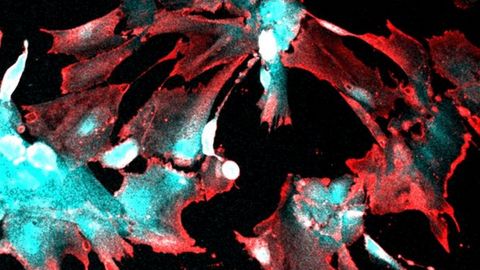

Células infectadas con el SARS-CoV-2

Células infectadas con el SARS-CoV-2 TITILOLA KALEJAIYE, DUKE UNIVERS | EUROPAPRESS